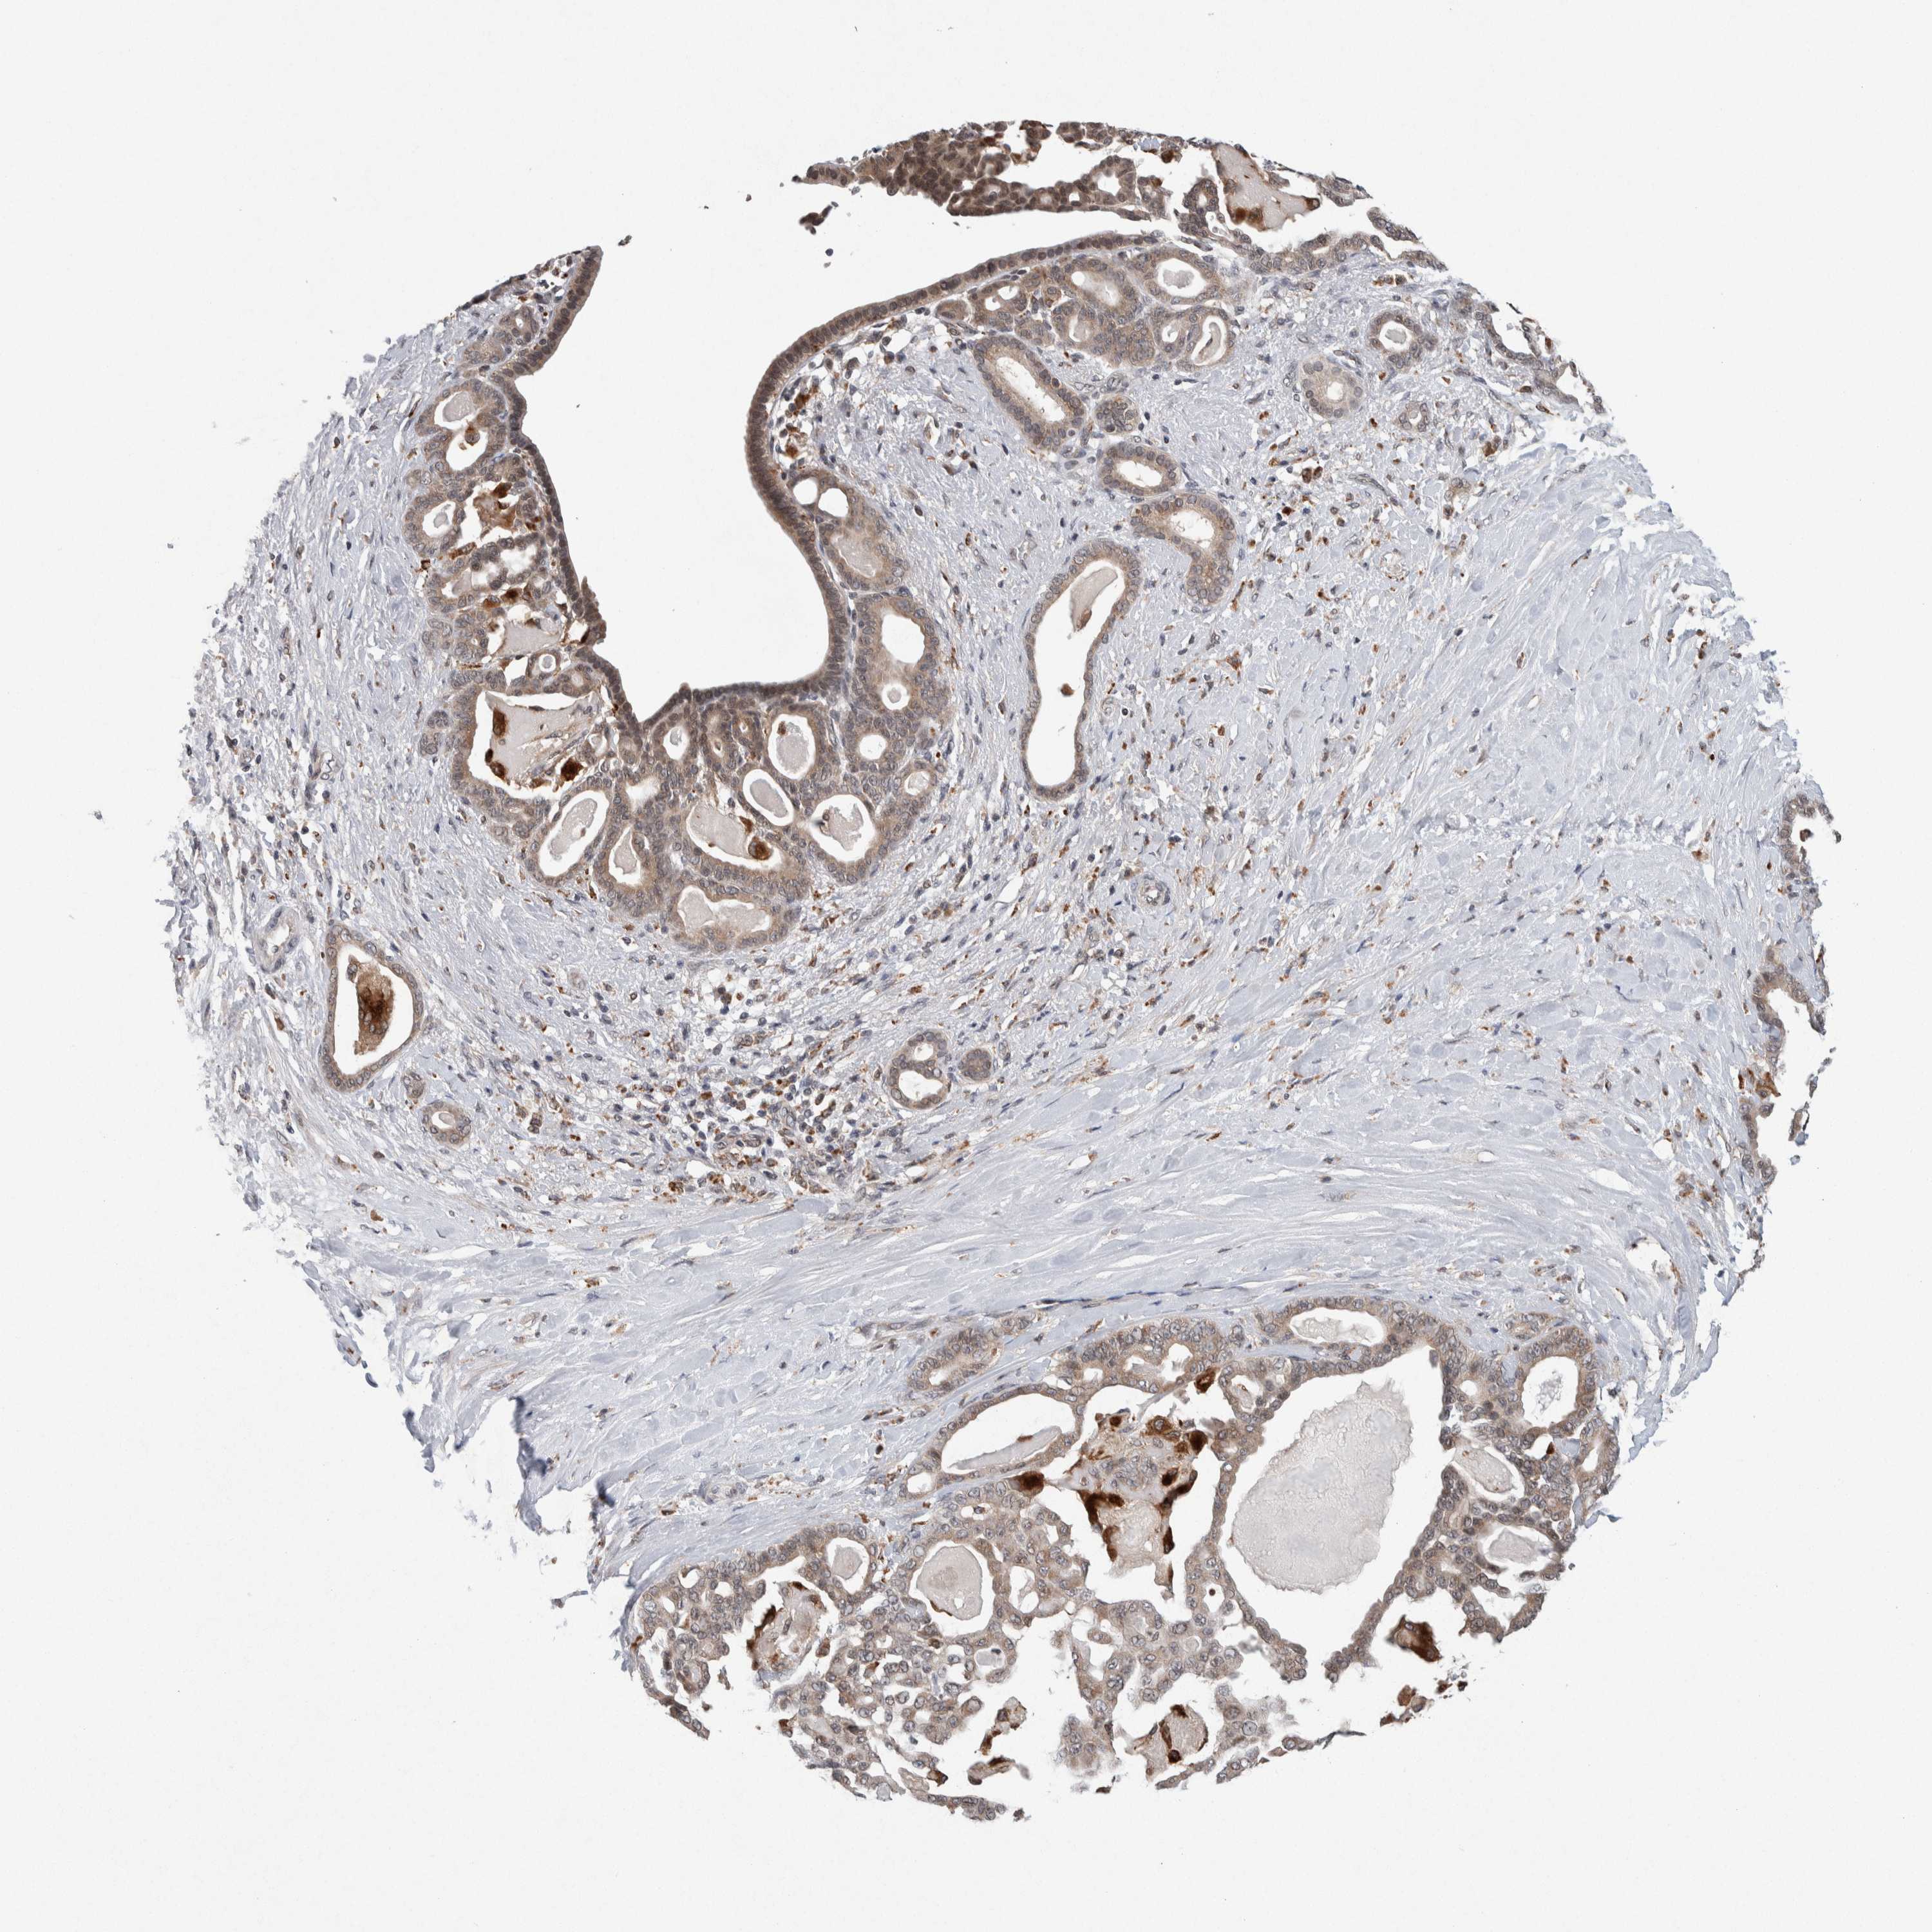

PANCREATIC CANCER - Protein expressioni

A mouse-over function shows sample information and annotation data. Click on an image to view it in a full screen mode. Samples can be filtered based on level of antibody staining by selecting one or several of the following categories: high, medium, low and not detected. The assay and annotation is described here.

Note that samples used for immunohistochemistry by the Human Protein Atlas do not correspond to samples in the TCGA dataset.

Antibody stainingi

Antibody staining in the annotated cell types in the current human tissue is reported as not detected, low, medium, or high, based on conventional immunohistochemistry profiling in selected tissues. This score is based on the combination of the staining intensity and fraction of stained cells.

Each image is clickable and will lead to virtual microscopy that enables deeper exploration of all samples and also displays staining intensity scores, fraction scores and subcellular localization as well as patient and tissue information for each sample.

Antibody HPA016049

Antibody CAB022588

Staining

High

Medium

Low

Not detected

Intensity

Strong

Moderate

Weak

Negative

Quantity

>75%

75%-25%

<25%

None

Location

Nuclear

Cytoplasmic/membranous

Cytoplasmic/membranous,nuclear

Adenocarcinoma, NOS

Adenocarcinoma, metastatic, NOS